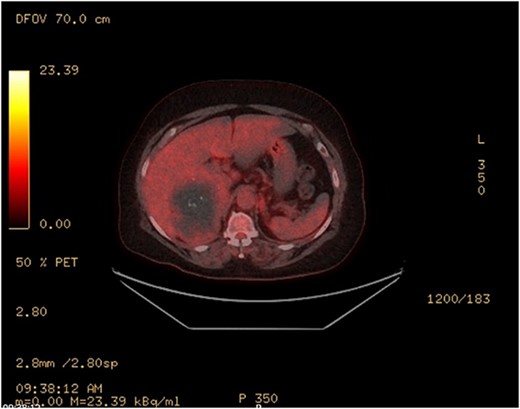

PET—large heterogenous complex right adrenal mass that measured up to 10 cm is largely photopenic with a mild peripheral rim of FDG accumulation (SUV max 3.4) at a level similar to adjacent physiologic hepatic activity.